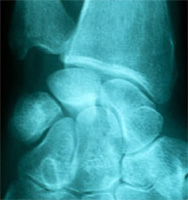

La chondrocalcinose est une arthropathie de précipitation, c’est-à-dire une maladie des articulations qui est souvent confondue avec l’arthrose : des cristaux (de pyrophosphate de calcium) se forment dans le liquide articulaire et se déposent sur les ligaments et les cartilages des articulations et les détruisent. Cette destruction est comparable à celle de la goutte qui est aussi une arthropathie de précipitation due à des cristaux d’acide urique. Les localisations principales de cette affection sont le genou et le poignet. L’affection évolue le plus souvent par crises aiguës: l’articulation qui devient chaude, avec un gonflement visible et des douleurs au mouvement. Ces crises durent de quelques jours à quelques semaines et laissent parfois une articulation déformée.

![]() |

Il arrive aussi que l’évolution soit progressive se manifestant par des douleurs articulaires et des déformations. Cette maladie débute en général après 50 ans , mais le plus souvent après 70 ans, ce qui la rend de plus en plus fréquente en raison de la longévité augmentée. Il existe des formes familiales où le début est plus précoce.

Ce sont les douleur du poignet ou du pouce avec gonflement lors des crises. L’affection peut aussi être découverte par hasard lors d’un traumatisme : pas de douleur, mais à l’examen, limitation des mouvements et de la force. Il n’y a pas de traumatisme dans les antécédents L’age est relativement avancé: 70 ans, en moyenne et l’atteinte est symétrique touchant les deux poignets et parfois les genoux. Parfois, enfin l’affection est révélée par un syndrome du canal carpien qui peut être aigu.

Les signes radiologiques sont souvent très important, même quand les signes cliniques sont modérés ou absents (formes asymptomatiques). Les signes caractéristiques sont: des calcifications, des pincements articulaires localisés ou généralisés, une sclérose osseuse, des géodes osseuses parfois volumineuses. Il n’y a pas d’ostéophytes ni de phénomènes de construction osseuse, ce qui permet de le distinguer de l’arthrose. Les trois localisations les plus typiques sont: la calcification du ligament triangulaire (unissant le radius à l’ulna (cubitus), le pincement isolé de l’articulation scapho-trapèzo-trapèzoïdienne, et l’atteinte des ligaments scapho-lunaire avec dissociation de ces deux os. Plus rarement l’articulation pisi-pyramidale et la médiocarpienne peuvent être atteintes.